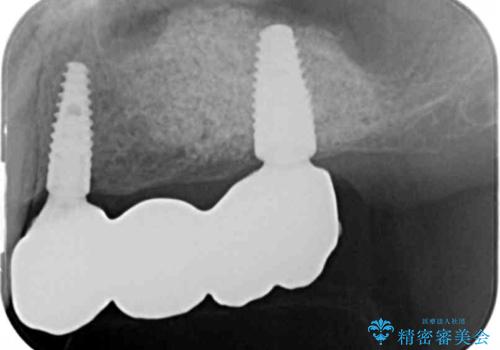

- 重度の虫歯により左上の歯を失い、インプラント治療は怖いため嫌厭して放置していたが、いよいよ食事に困りしっかりと噛めるようになりたいと希望され来院されました。

残存している小臼歯も虫歯が大きく保存が難しいため抜去を行い造骨を含めたインプラント治療を行います。

しっかりと造骨を行ったことでインプラント周囲には十分な量の骨が存在し安定したインプラント周囲環境を整えることができました。